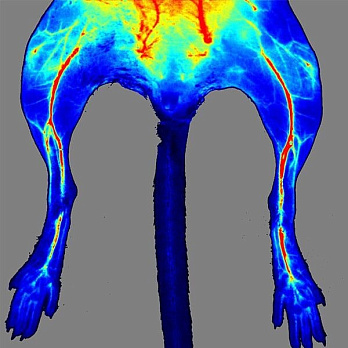

Системы MOIS предназначены для захвата и анализа изображений биолюминисцентных и флуоресцентных сигналов образцов тканей и живых организмов, полученных в формате in vivo и in vitro. Благодаря использованию высокочувствительной макрокамеры и высококачественных фильтров MOIS можно получать отличные изображения в режиме реального времени. Система имеет высокую производительность, а четыре канала (синий, зеленый, красный и ближнекрасный) позволяют получить визуализацию широкого спектра флуоресцентных белков и красителей, включая GFP и ICG. Анализ люминисцентных сигналов осуществляется при помощи соответствующего ПО, входящего в комплект поставки прибора. Простая конструкция системы MOIS отличается удобством в работе, быстротой и надежностью.

- определение эффективности и биологического распределения лекарственных препаратов, частиц наноформата и других молекул;

MOIS HT визуализирует флуоресценцию в видимом (VIS) и инфракрасном (NIR) спектре, биолюминисценцию in vivo и in vitro